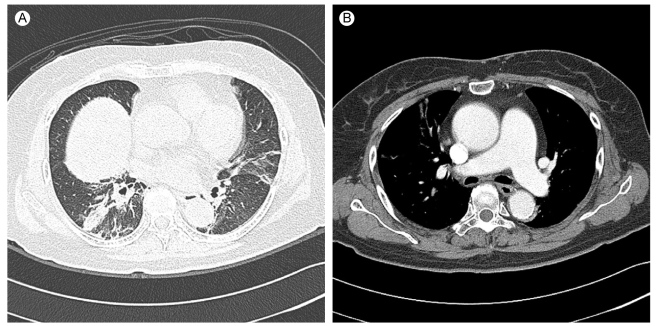

The initial chest X-ray showed a slightly reduced lung volume (Fig. 1A). The chest computed tomography (CT) scan showed no evidence of pulmonary thromboembolism, but there was bibasilar atelectasis (Fig. 2). Echocardiography revealed normal systolic and diastolic heart function.

Figure 2

Spiral computed tomography (CT) scan of the chest. (A) CT scan shows multifocal atelectasis in both lungs. (B) There was no definite evidence of an acute pulmonary thromboembolism.

Recently, several cases of MG with respiratory failure as a first manifestation have been reported [3-6]. In these studies, respiratory failure as an initial symptom was observed in 14 to 18% of the patients. Most of the patients presented with ocular and bulbar muscle involvement [7]. However, our patient showed no other neurological symptoms associated with MG. Therefore, we did not suspect MG initially. We tried to determine the cause of the respiratory failure. We did not find any evidence of a hypoxemic respiratory failure; there were no definite infiltrations, edema, effusion or pneumothorax on chest X-ray. There was no evidence of pulmonary thromboembolism on the chest CT scan and no evidence of intracardiac shunting or congestive heart failure on the echocardiography. Therefore, we suspected an acute ventilatory failure. Drugs or trauma that could cause ventilatory failure was ruled out. The electrolyte levels were within normal limits. Based on these results, we investigated the possibility of a neuromuscular disease, especially Guillain-Barre syndrome and myasthenia gravis, the most common and the second most common cause of neuromuscular disease, respectively. However, the cerebrospinal fluid was normal, and the neurophysiological studies showed evidence of myasthenia gravis.